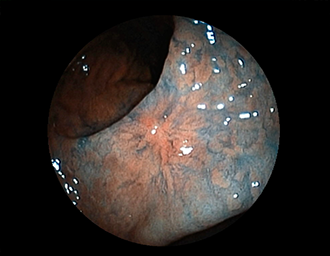

症例2:胃がん(66才男性)

術後胃(B-Ⅱope magen:十二指腸潰瘍手術)。吻合部の後壁側、軽度陥凹の白色病変を認める。生検:Group 5、Signent-ring cell carcinoma(印環細胞癌)と診断[早期胃癌]。高次医療機関へ紹介となり、残胃全摘術(リンパ節郭清)を行いました。

(通常画像)

(インジゴカルミン散布画像)